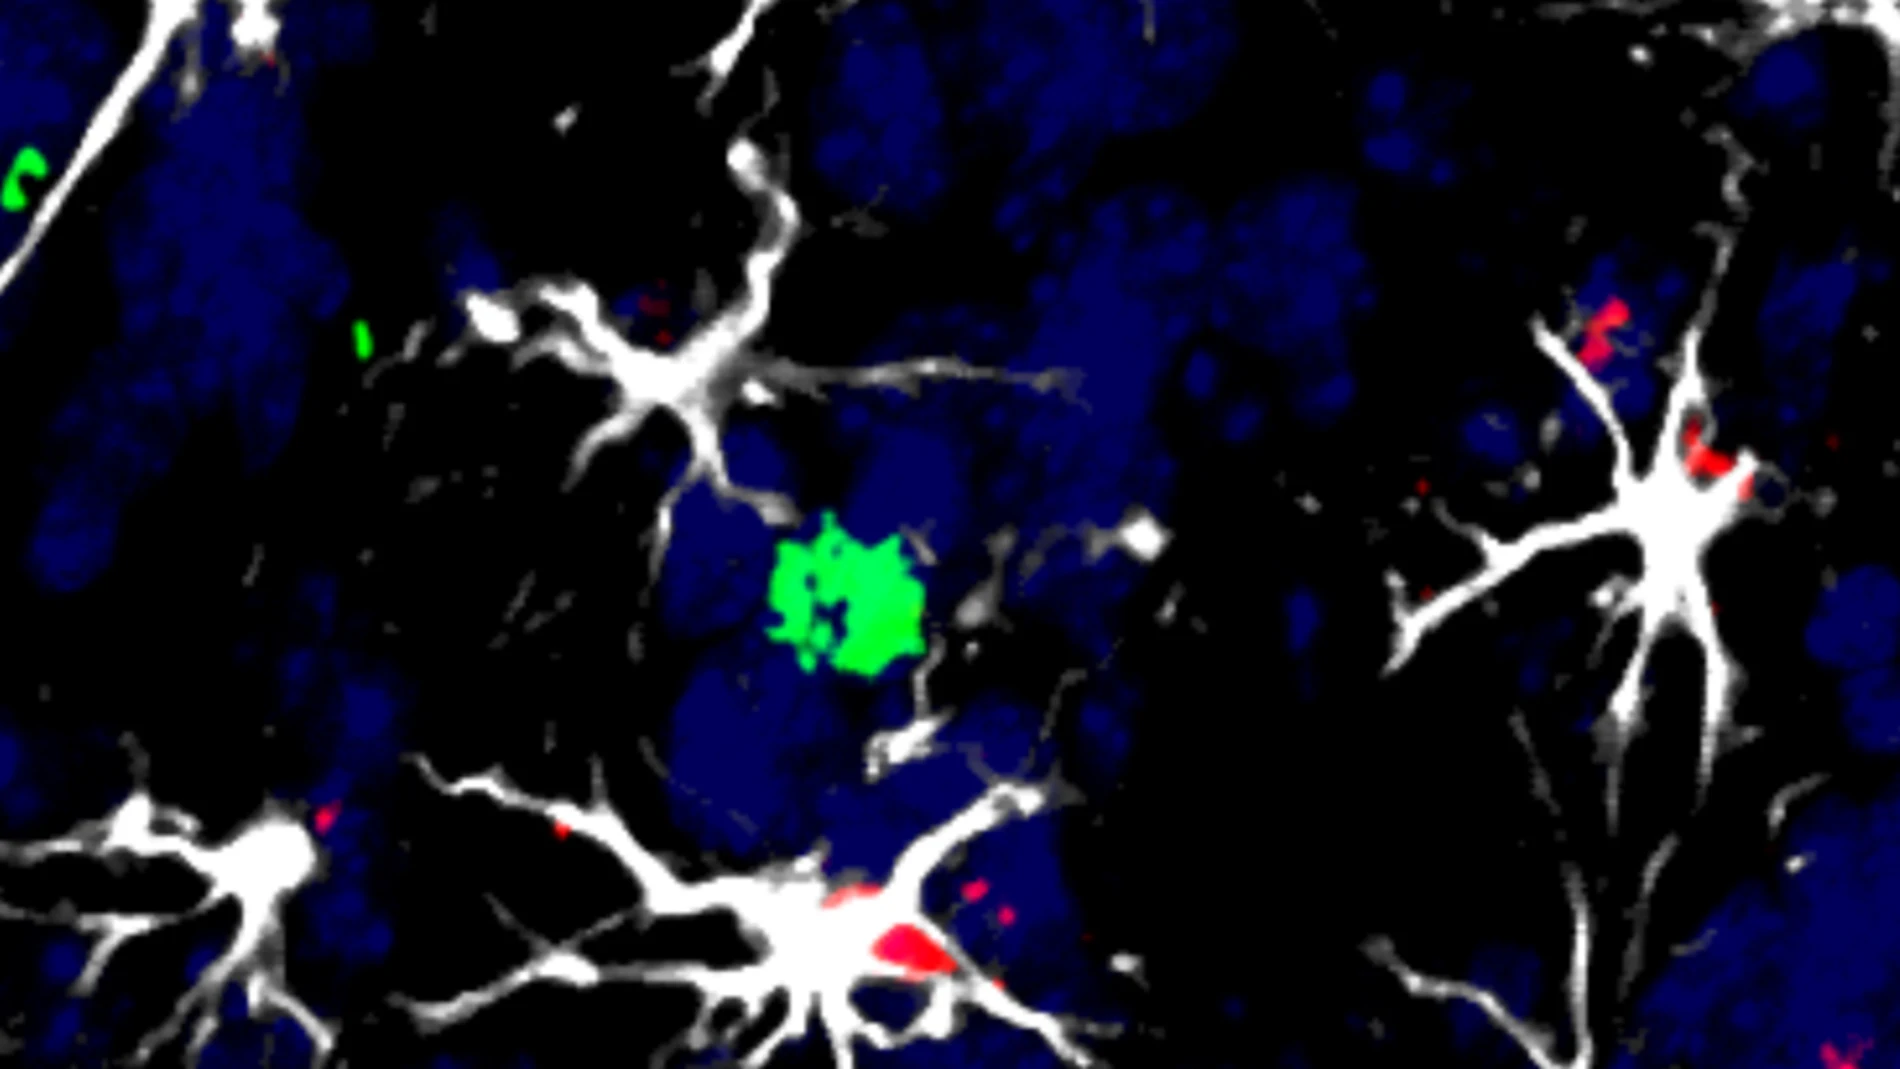

Un grupo internacional de investigadores, entre ellos españoles, ha creado una mini linterna molecular con un delgadísimo haz de luz capaz de llegar a regiones profundas del cerebro sin causar daño y de detectar metástasis cerebral u otras lesiones en ratones.

La nueva linterna molecular, aún en fase experimental, ilumina el tejido nervioso y, al hacerlo, informa de su composición química, lo que permite advertir de los cambios moleculares producidos por tumores, ya sean primarios o metastásicos, y también por lesiones como traumatismos craneoencefálicos.

En cuanto a aplicaciones concretas, el grupo que dirige Valiente en el CNIO ha usado la linterna molecular en modelos experimentales de metástasis cerebral: "Como ocurre con los pacientes, hemos visto frentes del tumor que sueltan células que escaparían a la cirugía", señala.